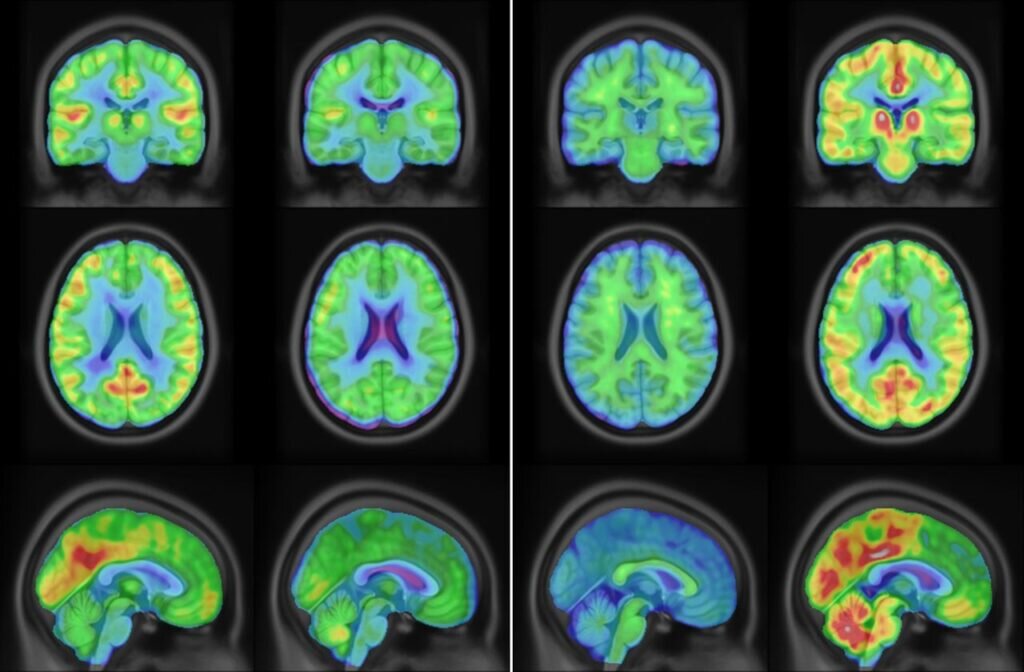

Изображения, полученные с помощью ПЭТ / © Shelley N. Acuff. et al.

Авторы исследования также испытали новую метку на людях. Четырем мужчинам и четырем женщинам в возрасте 22-31 года ввели 18F-Холестифай и сделали им ПЭТ головного мозга. Молекула-метка хорошо накапливалась в коре больших полушарий, таламусе и базальных ганглиях — тех частях мозга, где цитохром CYP46A1 экспрессируется особенно сильно.